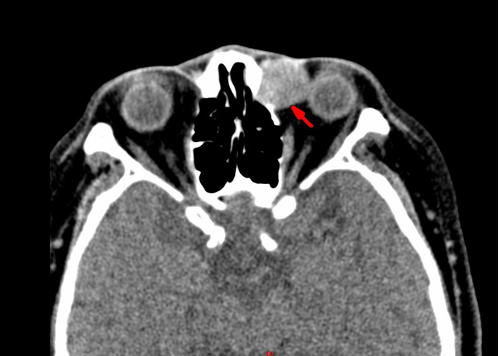

讲座|左泪囊肿瘤一例病例分享

病理诊断:(左泪囊)DEK-AFF2 融合相关的鳞状细胞癌。

DEK-AFF2 癌是鼻腔鼻窦非角化性鳞状细胞癌的罕见亚型,2022 年 WHO 头颈部肿瘤分类纳入其中。好发于男性(男女比例 3:2),年龄 18~79 岁(中位 58 岁),多见于鼻咽、鼻腔和鼻窦等部位,泪囊发病罕见